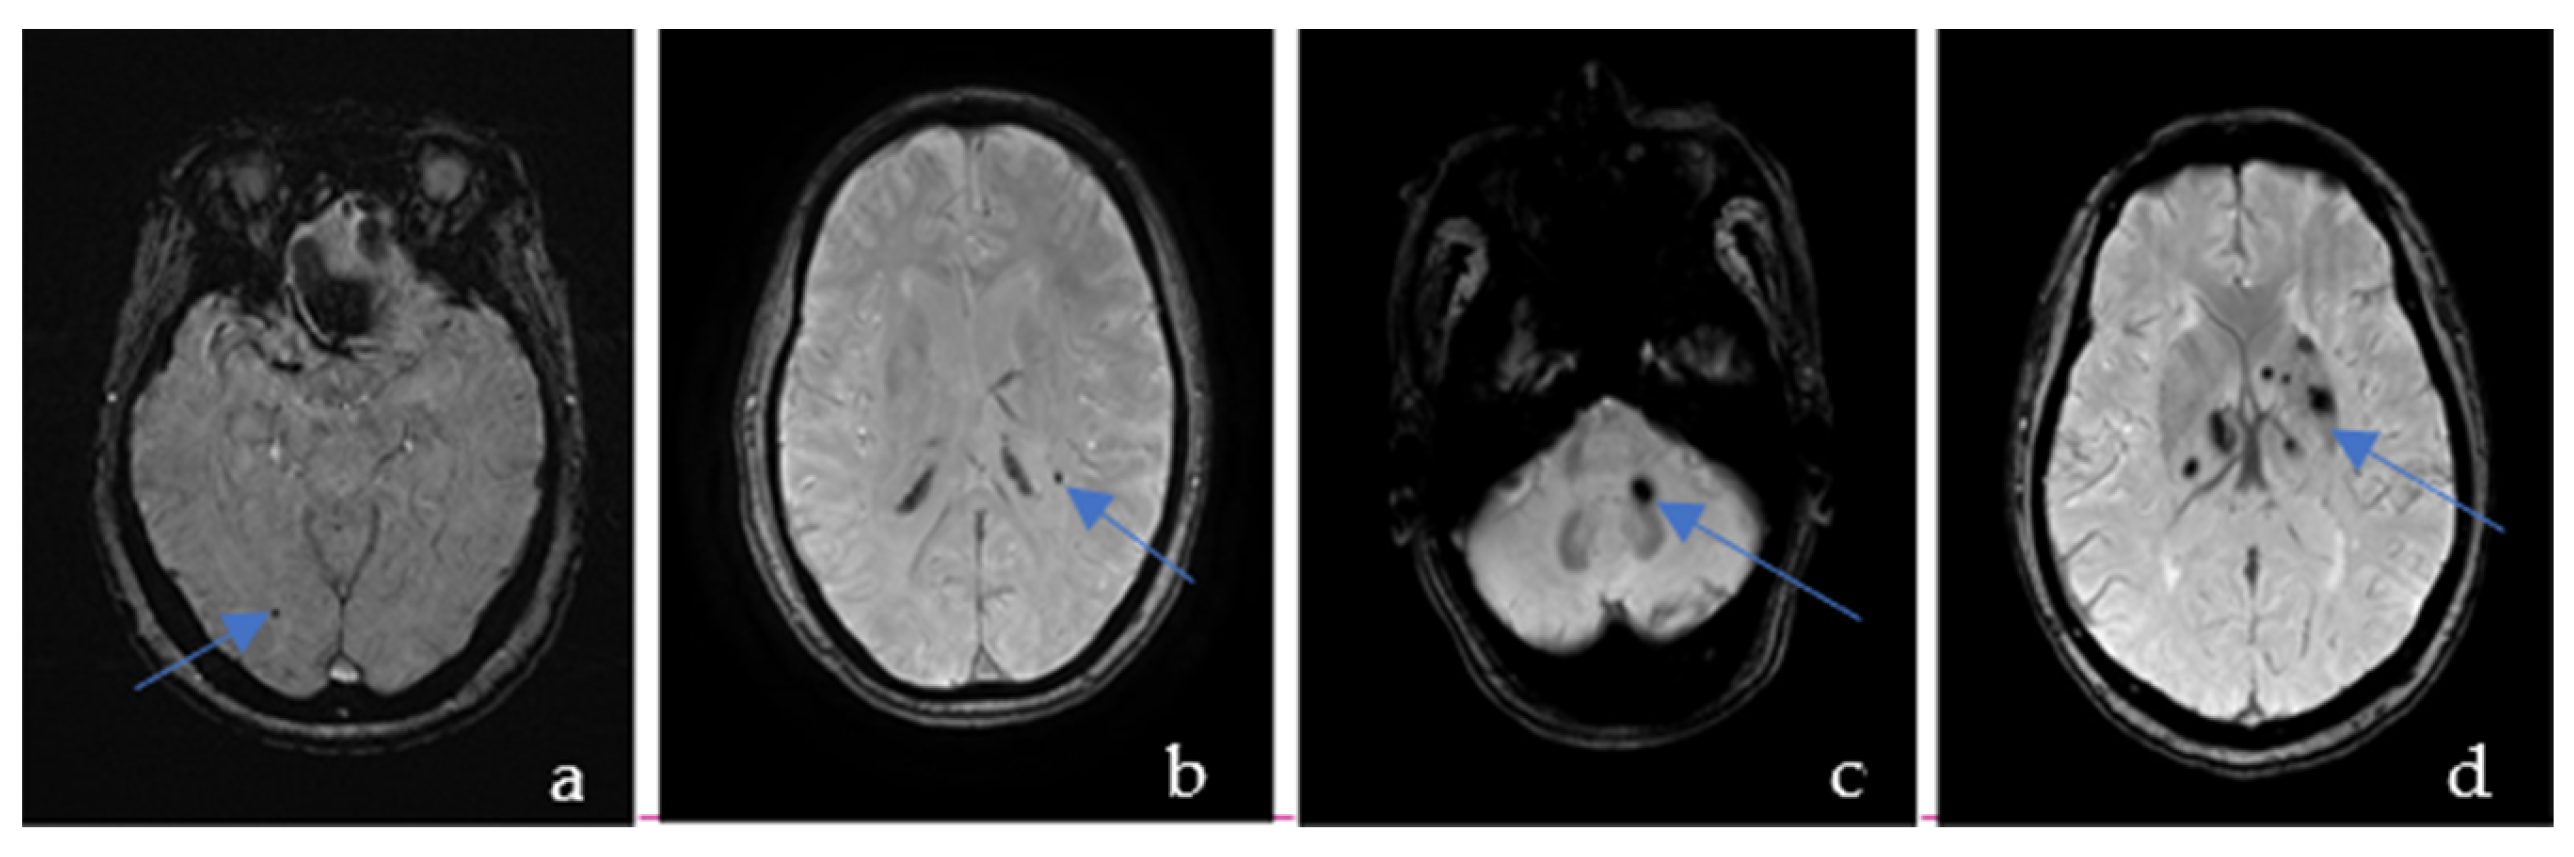

CMBs are visible as the hypointense ovoid signal on T2-weighted gradient-recalled echo and SWI because of the paramagnetic properties of the blood breakdown product hemosiderin [11]. These lesions may be up to 10 mm in diameter, but the most common diameter is 2–5 mm [12]. According to the Microbleed Anatomical Rating Scale (MARS) [13], CMBs were classified into deep, lobar, and infratentorial CMBs (Figure 1). Lobar regions included cortical and subcortical regions (including subcortical U fibers). Deep regions comprised the basal ganglia, thalamus, internal capsule, external capsule, corpus callosum, and deep and periventricular white matter (DPWM). Infratentorial regions included the brainstem and cerebellum. CMBs distributed in 2 or more areas were named mixed regions. All areas are provided in the anatomical diagram for easy reference. We did not distinguish between definite and possible CMBs but only counted their total numbers as per MARS.

Figure 1. Susceptibility-weighted imaging showing an example of the cerebral microbleeds in the lobar (a), deep (b), infratentorial (c), and mixed regions (d).